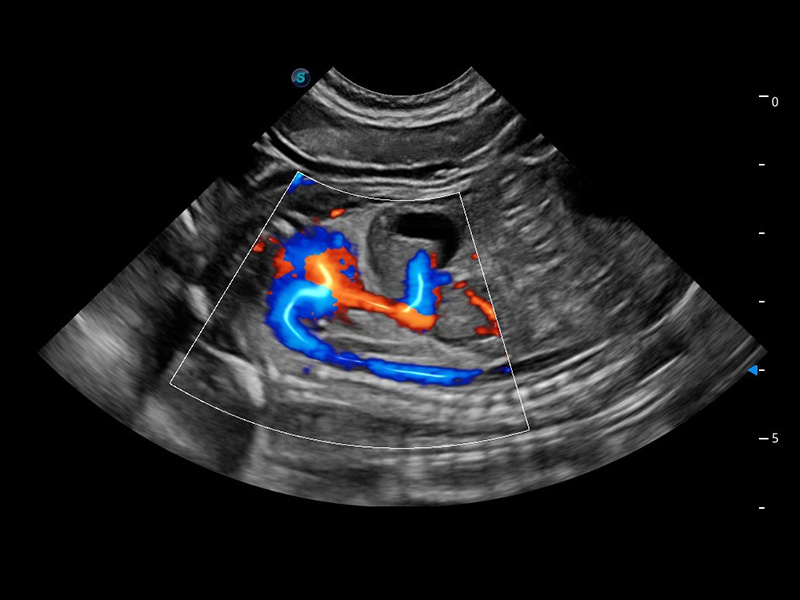

ProPet 60 作为一款高端台式动物超声设备,为动物医生的日常诊断提供了一系列贴合动物临床需求、解决临床实际问题的高级成像功能。凭借全系列高清探头,满足医生对腹部、心脏、生殖、浅表、肌骨等成像的所有需求,切实帮助您提升检查效率,提高诊断信心。